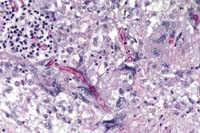

Case 27-3. Heart valve. Fungal hyphae with non-parallel sides are partially surrounded and being phagocytized by multinucleated giant cells which are admixed with fibrin, histiocytes and small lymphocytes. PAS 40X

Contributor's Diagnosis and Comments: Vegetative mural endocarditis of the left atrium caused by a fungus of the Zygomycetes class.

The vegetation contains fibrin, amorphous proteinaceous material, erythrocytes, a mixture of leukocytes, cellular detritus and myriads of fungal hyphae. Several multinucleate giant cells are present in the area of attachment to the endocardium. Fibroplasia is present in that region also. Fungal hyphae are nonseptate, branch irregularly and do not have parallel sides. These are characteristics of the Zygomycetes class, which includes several pathogenic genera such as Absidia, Mucor and Rhizopus spp. Cultures were not attempted. Microscopic granulomas were found adjacent to the major bronchus of one lung. Similar fungal hyphae were present there and we conclude that the lesion in the left atrium developed secondary to the pulmonary infection.

AFIP Diagnosis: Heart: Endocarditis, vegetative, heterophilic and granulomatous, valvular and mural, severe, with focally extensive myocarditis and epicarditis, and numerous fungal hyphae, conure, avian, etiology consistent with a mucoraceous zygomycete.

Conference Note: Conference participants discussed the morphologic differences between Aspergillus sp., common pathogens of birds, and Zygomycetes, which are occasionally seen in immunocompromised or debilitated birds. Aspergillus sp. hyphae are typically 3 to 6 mm wide, septate and branched. Branching is dichotomous and often at acute angles. Typical mucoraceous hyphae vary from 5 to 20 mm wide and branch nondichotomously at right angles. The hyphal walls are thin and often become twisted or folded.